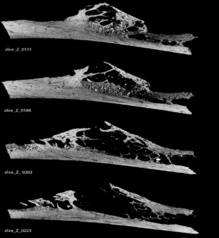

Un grupo internacional de investigadores, liderado por David Frayer, de la Universidad de Kansas (EE UU), ha observado el caso más antiguo de un tumor óseo encontrado en las costillas de un espécimen de neandertal en Croacia. El estudio, publicado esta semana en la revista PLOS ONE, revela que al menos un neandertal sufrió un cáncer que es común en los seres humanos actuales: la displasia fibrosa, un trastorno de causa desconocida, poco común y benigno, caracterizado por una proliferación tumoral de tejido fibroóseo. Este descubrimiento, datado en torno a hace 120.000 años, posee más de 100.000 años de diferencia con las evidencias previas que se tenían de estas patologías, que las situaban, por primera vez, entre hace 1.000 y hace 4.000 años. Los autores destacan que la costilla cancerosa, recuperada en la famosa excavación arqueológica de la ciudad croata de Krapina, es una muestra incompleta, por lo que no pudieron definir los efectos en la salud que dicho tumor podría haber tenido sobre este individuo. “Este caso demuestra que los neandertales, que vivían en un medio ambiente no contaminado, fueron susceptibles al mismo tipo de cáncer que los humanos", señala Frayer. Por su parte, Janet Monge, paleoantropólogo del Museo Penn de Pensilvania (EE UU) y primera autora del trabajo, apunta que "este tumor puede proporcionar otro vínculo entre los neandertales y las poblaciones modernas" Más información SINC